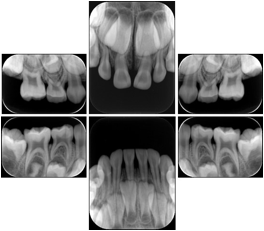

2. A patient requests cosmetic surgery to enhance their facial appearance. The case requires consultation between an orthodontist in New York and an oral surgeon in California. The cephalometric series of 2D projections constructed from the volumetric CT data that is used for the discussion is arranged by a Structured Display for transfer between the two practitioners.

Cephalometric Series Structured Display

Figure OO-2. Cephalometric Series Structured Display